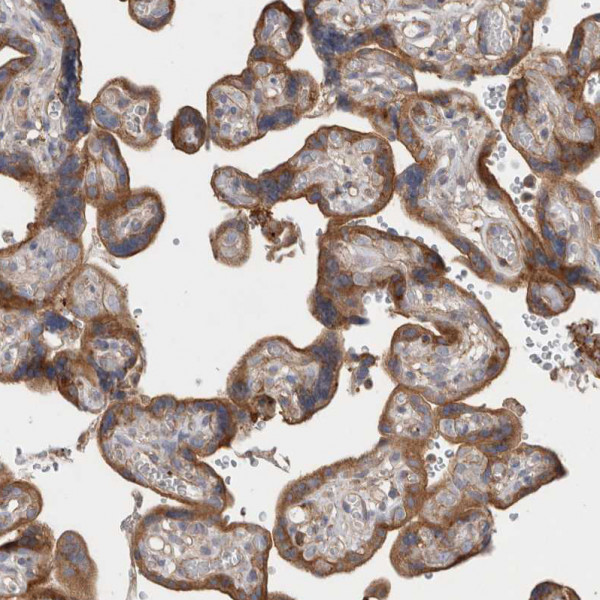

Product information "Anti-GPER1"

Protein function: G-protein coupled estrogen receptor that binds to 17-beta- estradiol (E2) with high affinity, leading to rapid and transient activation of numerous intracellular signaling pathways. Stimulates cAMP production, calcium mobilization and tyrosine kinase Src inducing the release of heparin-bound epidermal growth factor (HB-EGF) and subsequent transactivation of the epidermal growth factor receptor (EGFR), activating downstream signaling pathways such as PI3K/Akt and ERK/MAPK. Mediates pleiotropic functions among others in the cardiovascular, endocrine, reproductive, immune and central nervous systems. Has a role in cardioprotection by reducing cardiac hypertrophy and perivascular fibrosis in a RAMP3-dependent manner. Regulates arterial blood pressure by stimulating vasodilation and reducing vascular smooth muscle and microvascular endothelial cell proliferation. Plays a role in blood glucose homeostasis contributing to the insulin secretion response by pancreatic beta cells. Triggers mitochondrial apoptosis during pachytene spermatocyte differentiation. Stimulates uterine epithelial cell proliferation. Enhances uterine contractility in response to oxytocin. Contributes to thymic atrophy by inducing apoptosis. Attenuates TNF-mediated endothelial expression of leukocyte adhesion molecules. Promotes neuritogenesis in developing hippocampal neurons. Plays a role in acute neuroprotection against NMDA-induced excitotoxic neuronal death. Increases firing activity and intracellular calcium oscillations in luteinizing hormone-releasing hormone (LHRH) neurons. Inhibits early osteoblast proliferation at growth plate during skeletal development. Inhibits mature adipocyte differentiation and lipid accumulation. Involved in the recruitment of beta-arrestin 2 ARRB2 at the plasma membrane in epithelial cells. Functions also as a receptor for aldosterone mediating rapid regulation of vascular contractibility through the PI3K/ERK signaling pathway. Involved in cancer progression regulation. Stimulates cancer-associated fibroblast (CAF) proliferation by a rapid genomic response through the EGFR/ERK transduction pathway. Associated with EGFR, may act as a transcription factor activating growth regulatory genes (c-fos, cyclin D1). Promotes integrin alpha-5/beta-1 and fibronectin (FN) matrix assembly in breast cancer cells. [The UniProt Consortium] Buffer: 40% glycerol and PBS (pH 7.2). 0.02% sodium azide is added as preservative. Highest antigen sequence identity to mouse: 56% and to rat: 55%

| Application: | IHC |